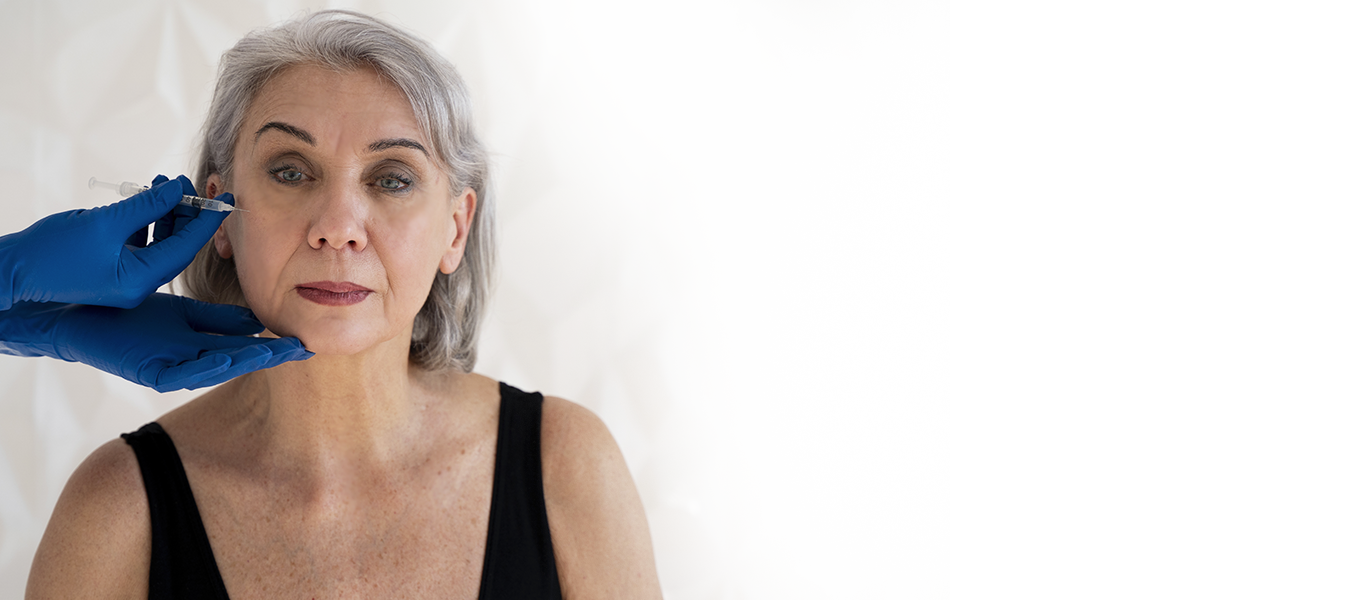

Toxina botulínica (Botox)

BOTOX MÉDICO. Para reducir arrugas dinámicas (frente, entrecejo) y tratar hiperhidrosis axilar/palmar con resultados en 72 horas.

Con BOTOX logramos un efecto natural, sin expresión "congelada" Duración de 4-6 meses. Aplicación rápida e indolora que logra la prevención de nuevas arrugas.

La Dra. Fernández, dermatóloga con especialización en estética médica y amplia experiencia en rejuvenecimiento facial, emplea técnicas precisas para resultados medibles y naturales. Seguimiento personalizado en cada caso. Tu mejor opción en Guatemala para tratamientos antiaging.

Reduce arrugas dinámicas en 72h

Efecto natural (sin "cara congelada")

Controla hiperhidrosis axilar/palmar

Dosaje milimétrico con aguas ultrafinas (31G)